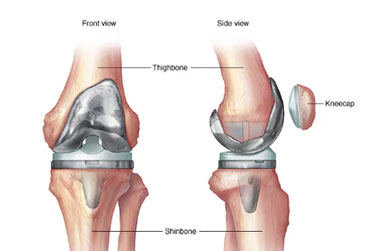

Dr Prateek Kumar is a highly qualified compassionate orthopaedic surgeon with over 15yrs of experience in field of Orthopaedic & Arthroplasty.He has received his medical education from renowned Institutions in India & has continuously updated his knowledge to stay at the forefront of medical advancement. Dr.Prateek Kumar is committed to providing the best possible care to his patients ensuring their comfort and well being throughout their treatment.